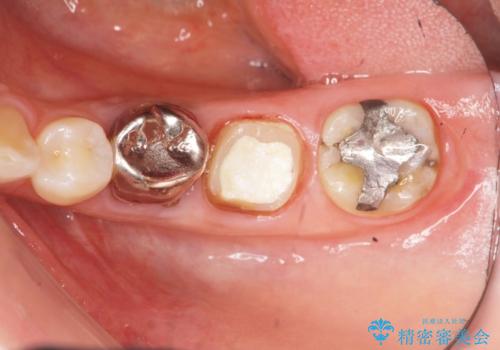

- 大人になってからも残っていた乳歯が揺れ始め、抜歯を覚悟しインプラント治療を希望して来院されました。

X線写真より、乳歯は抜歯が必要な状態でインプラントは小臼歯の埋伏により難しい状況であったのでブリッジによる補綴を選択しました。

ブリッジ治療の予知性を高めるために、虫歯の徹底的な除去に加え縁上歯質を確保するための歯周外科手術、マイクロスコープを用いた精密根管治療を行う治療計画としました。